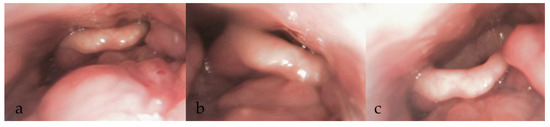

3.3. During DISE (Figure 1)

3.3.8. Documentation